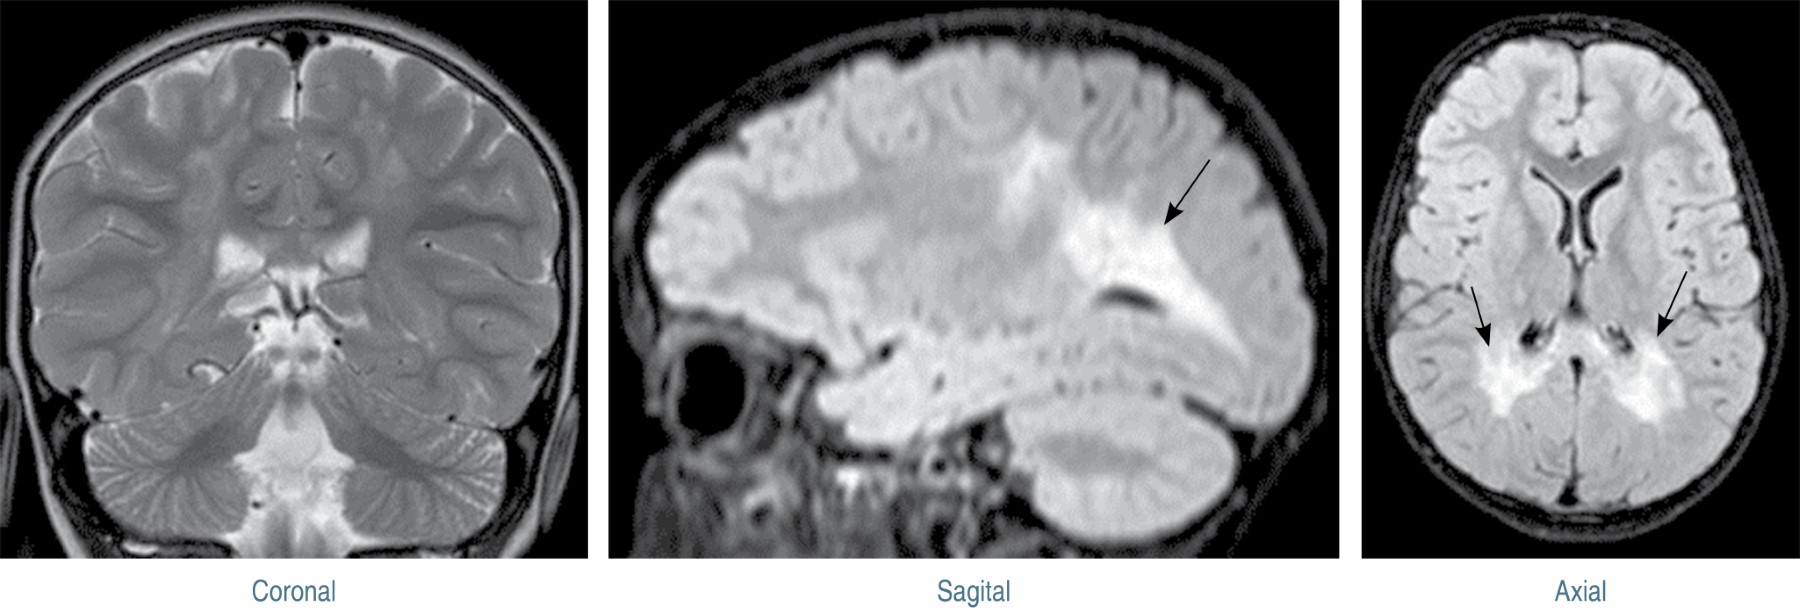

Neuropsychological profile of a patient with late infantile Krabbe disease and visual agnosia

Krabbe disease is a type of autosomal recessive lysosomal leukodystrophy caused by deficiency of the enzyme galactosylceramidase. The results of the neuropsychological evaluation in a three-year-old boy with apperceptive visual agnosia and prosopagnosia are presented.

Figure 1